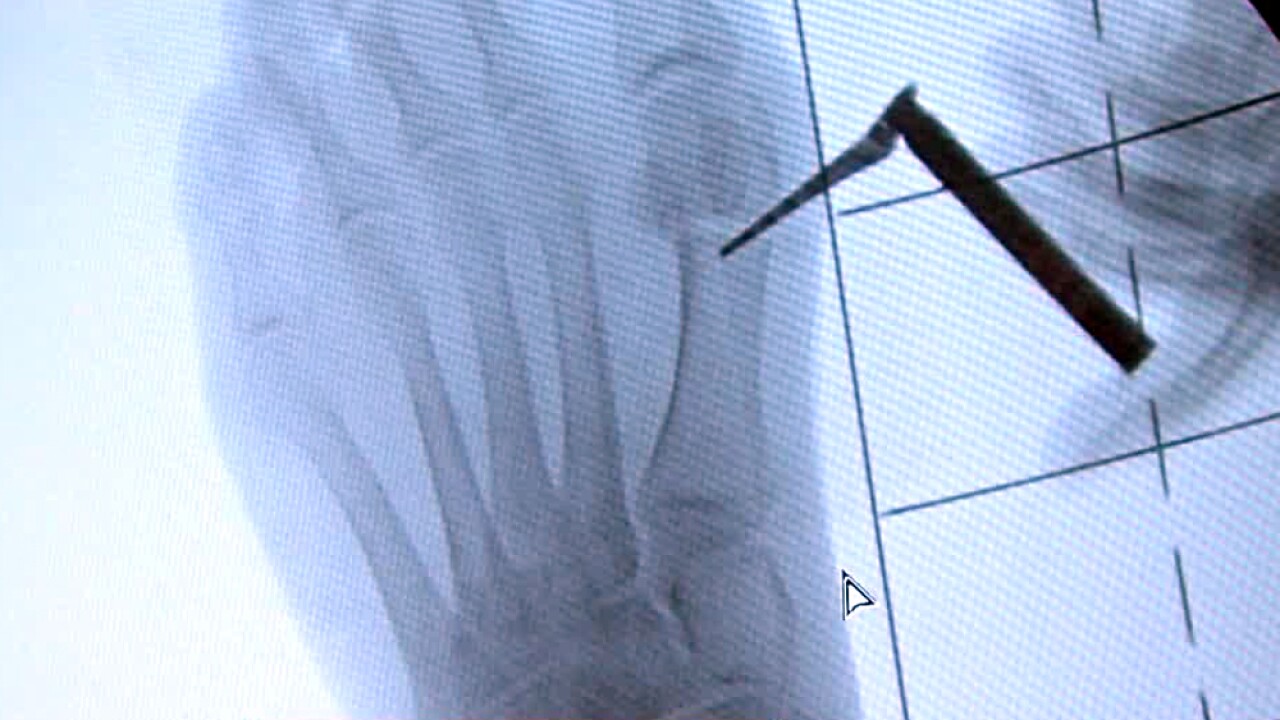

Dr. Bradley Lamm with the Paley Institute in West Palm Beach has spent the last five years inventing an internal device and step-by-step technique.

Lamm created an internal device called a mini bunion by crossroads.

Lamm described this as a minimally-invasive surgery where a device is entered through a tiny incision.